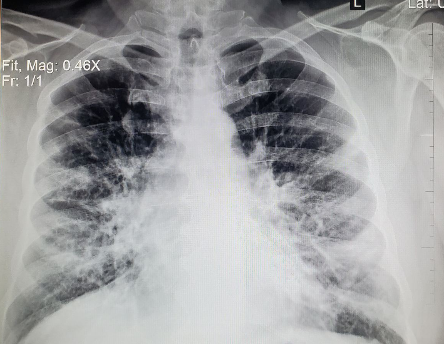

9.i se i PCR test. Naravno treba uraditi i osnovnu laboratoriju : krvna u sliku,CRP i na osnovu svega toga se pacijentu da odgovarajuća terapija. Dakle, kod delta soja, simptomi samo prvih dana liče na alergiju i grip. Ali, vrlo brzo može doći do pogoršanja, pojave pneumonije⬇️

10.Potrebe za bolničkim lečenjem sa neizvesnim ishodom.I posle izlečenja veoma čestim Long kovidom sa preko dvesta simptoma.O teškim mukama koje preživljava pacijent i porodica, da i ne govorimo. A postoji tako jednostavno rešenje!